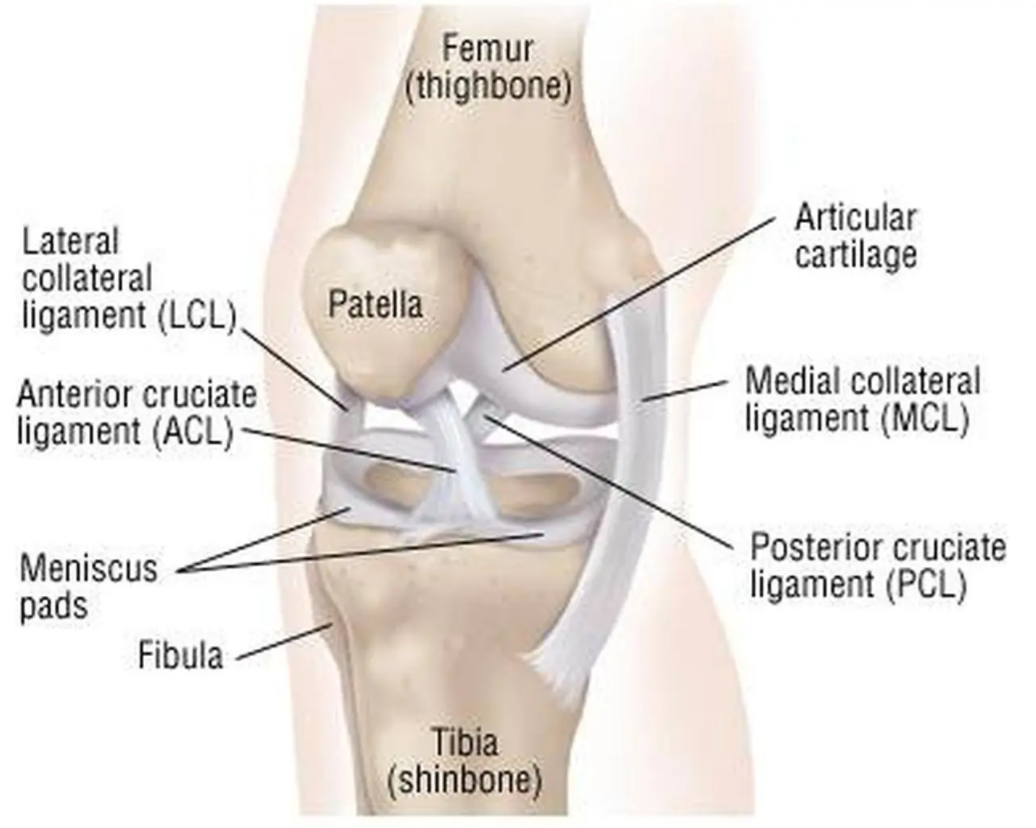

Cruciate ligament connects bone and bone. The role is to strengthen the stability of the joint, so as to avoid injury. When suffering from violence or non-physiological activities, ligaments are stretched beyond their tolerance, resulting in injury.

Cruciate ligament injury is very common in daily life. At present, many ligament reconstruction operations are based on the experience of doctors, and errors are inevitable. Extraction and reconstruction of cruciate ligament insertion is very important, which can help doctors to analyze and predict before surgery, and improve the success rate of surgery.